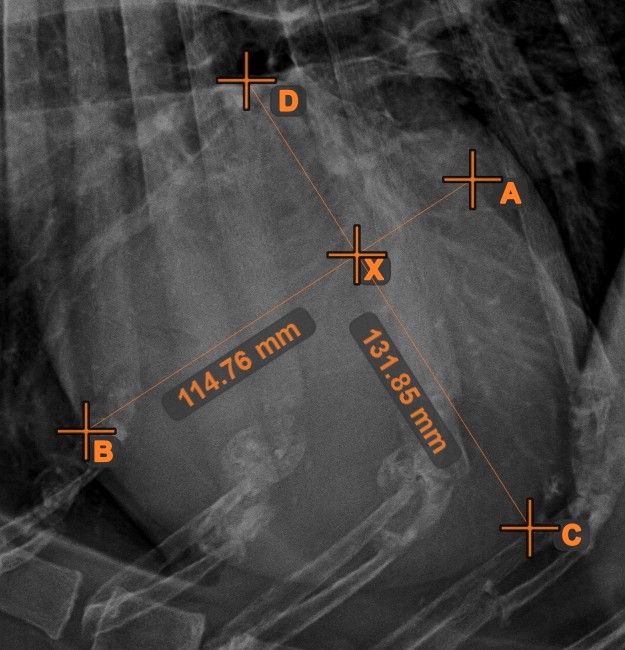

Line Intersection¶

Quickly and accurately locate and mark the intersection point between two existing lines by using the Line Intersection tool.

Select the tool from the left toolbar and assign it to one of the available mouse buttons. Select two lines that have already been drawn on the scene to complete the measurement. The intersection point of the line will be automatically calculated and marked on the scene. The intersection point of two lines will always be marked with the letter X.

Information

If two lines do not intersect directly, the intersection point of their extended projections on the scene will be marked.